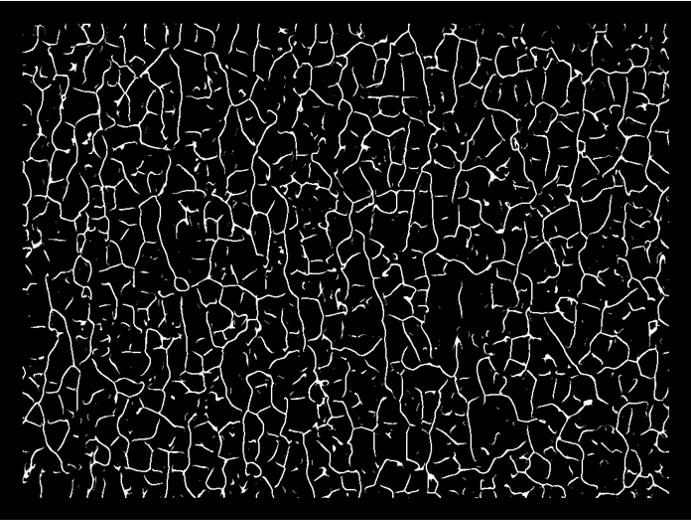

In-vivo desquamation

The detection and quantification of skin flakes in in vivo images make it possible to generate a useful index for studies on dry skin.

Microrelief sharpness

This index helps identify visible skin furrows, which are often associated with dry skin (accumulation of dead skin cells).

This analysis thus refines the evaluation of smoothing and moisturizing skincare products.